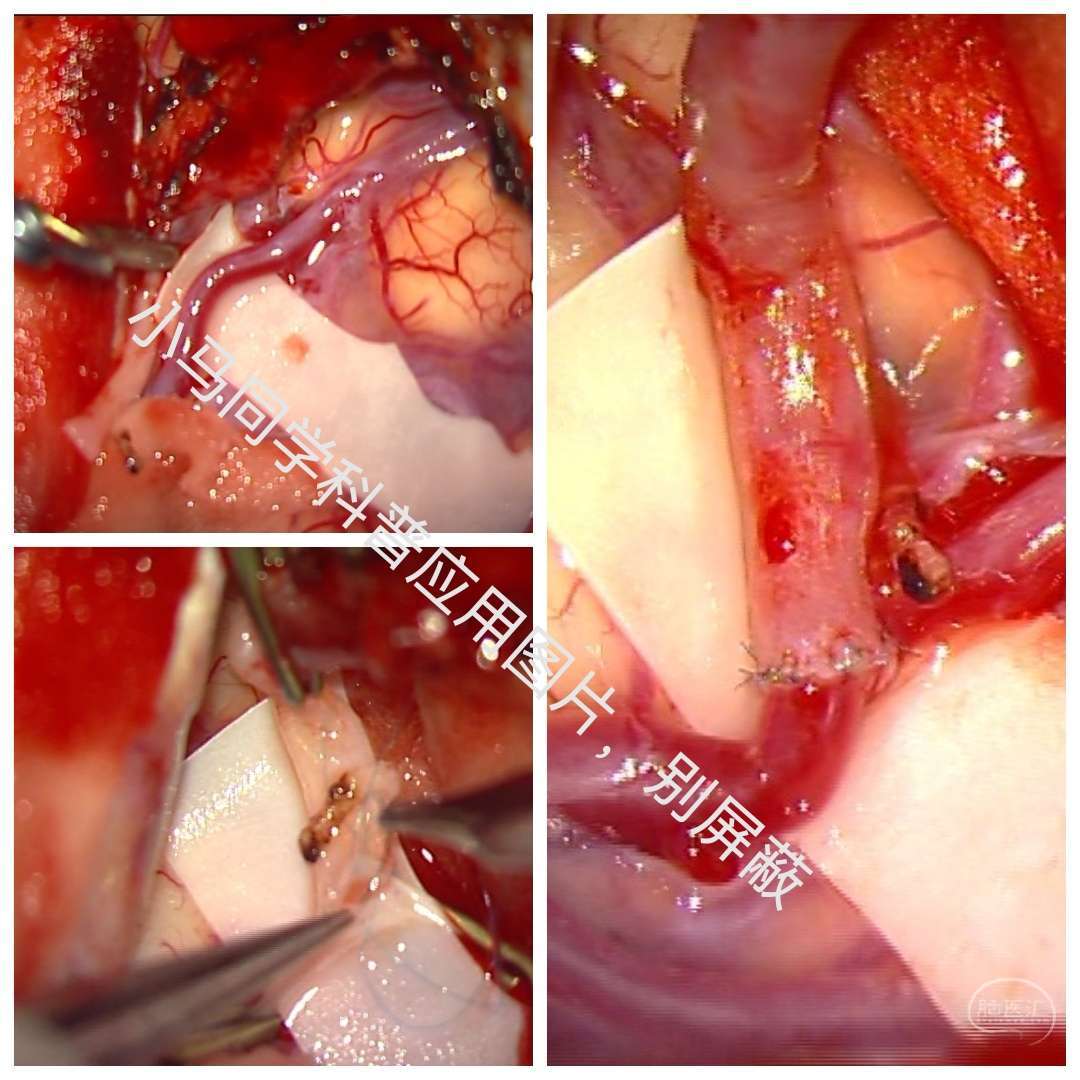

术中暴露充分颈动脉,切开颈内动脉后可见粥样斑块,切除斑块,缝合,一气呵成!天下武功,唯快不破。。。